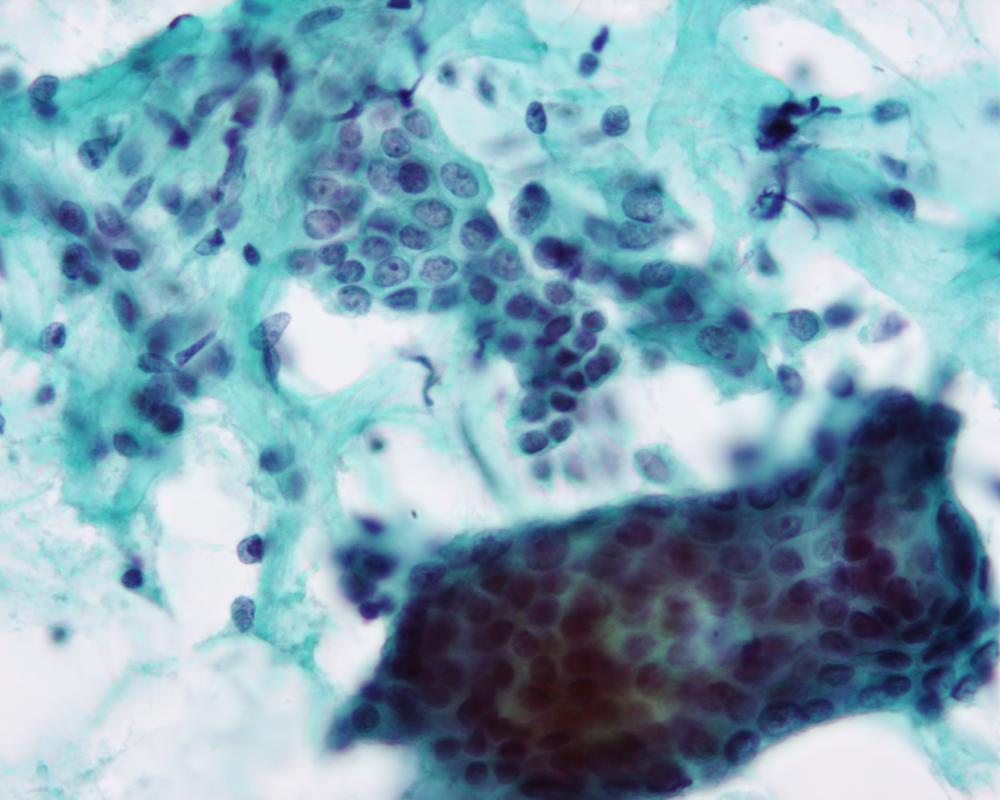

第37回日本臨床細胞学会九州連合会学会(佐賀)スライドカンファレンス症例5

出題:○大石 善丈 飯塚病院病理科

| 採取部位 | 子宮内膜 | 採取方法 | 擦過法 |

臨床所見

既往歴:10カ月前に右肺下葉腺癌にて右中下葉切除術。術後病理診断は乳頭型腺癌、pT2aN2M0 StageIIIA.

現病歴:肺癌の経過観察中、腫瘍マーカーのCEAが上昇したためPETを施行され、子宮体部に異常集積が認められた。子宮体癌が疑われ、内膜細胞診が提出された。

| 正解 | 4.肺腺癌の子宮転移 |